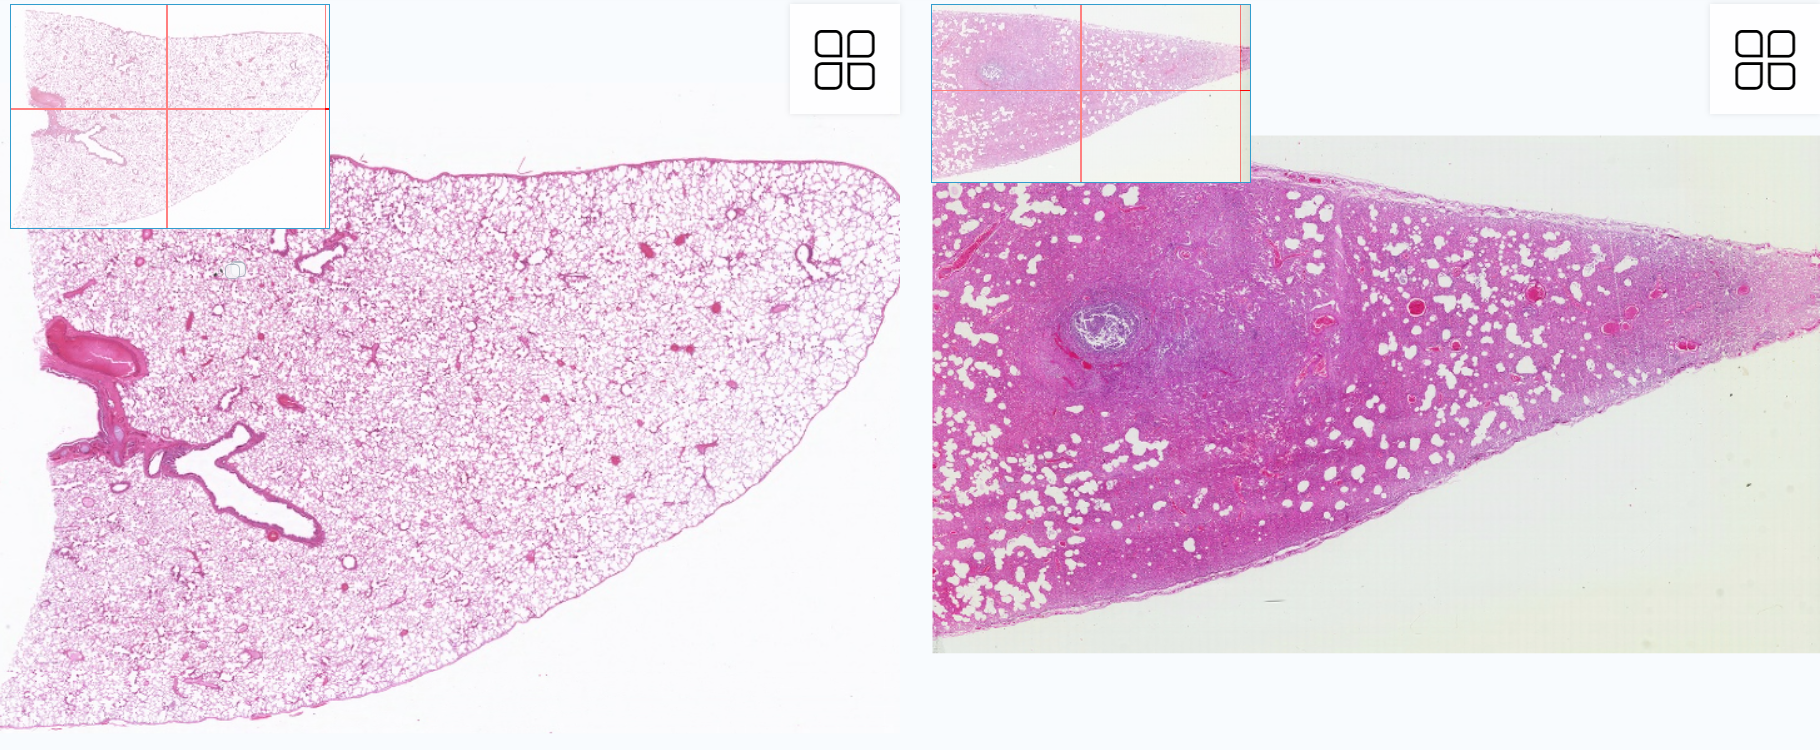

肺实质可区分为导气部(小支气管、细支气管及终末性支气管)和呼吸部(呼吸性细支气管、肺泡管、肺泡囊和肺泡)。低倍镜:覆盖在肺表面的浆膜是由一层间皮(单层扁平上皮)盖着结缔组织构成的。肺的组织由很多空泡状的结构(肺泡)组成,肺泡之间可见各级支气管。导气部高倍镜:(1)肺泡管:管壁结构少,呈一系列结节状膨大。(2)肺泡:肺泡壁很薄,为一层肺泡上皮,Ⅰ型肺泡细胞呈扁平状,Ⅱ型肺泡细胞散在分布,该细胞呈立方形,核大而圆,胞质着色浅。(3)肺泡隔:位于相邻肺泡上皮之间,有丰富的毛细血管及少量结缔组织(弹性纤维HE染色看不见)。

1.全景图